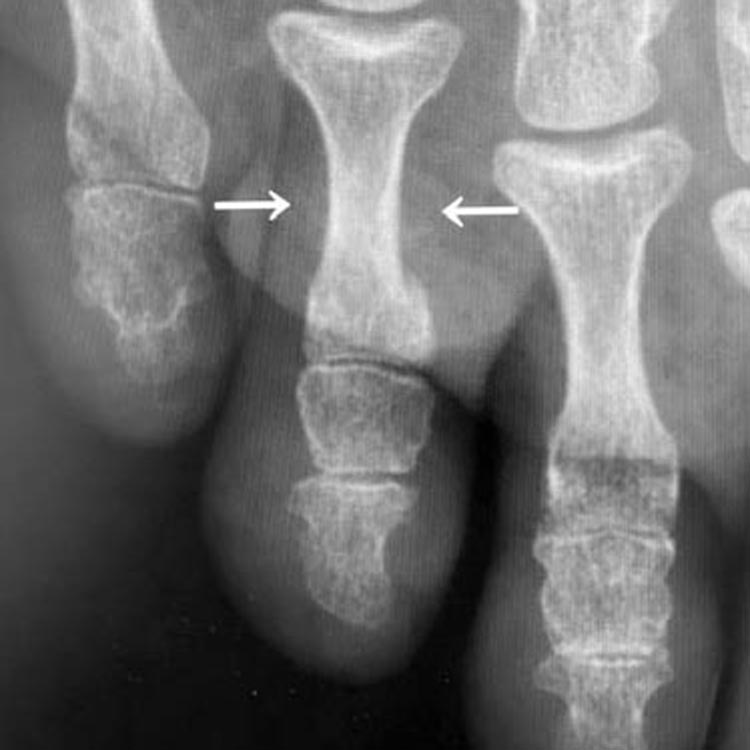

受傷1週後のレントゲン写真

受傷1週後(矢印が骨折部です)